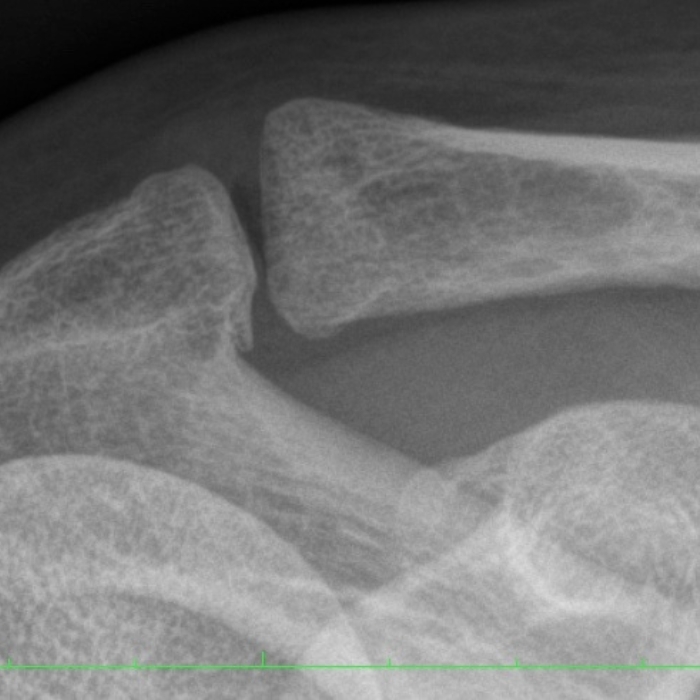

Zmiany zwyrodnieniowe stawu barkowo-obojczykowego

(AC joint arthritis)

Aby rozpoznać zmiany zwyrodnieniowe stawu barkowo-obojczykowego konieczne jest badanie kliniczne polegające na ocena ruchomości i funkcji poszczególnych elementów barku. Jako badania dodatkowe wykonuje się RTG i USG barku.